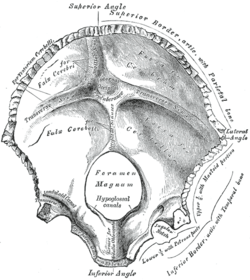

The foramen magnum (Latin: great hole) is a large oval opening (foramen) in the occipital bone of the skull in humans and various other animals. It is one of the several oval or circular openings (foramina) in the base of the skull. The spinal cord, an extension of the medulla, passes through the foramen magnum as it exits the cranial cavity. Apart from the transmission of the medulla oblongata and its membranes, the foramen magnum transmits the vertebral arteries, the anterior and posterior spinal arteries, the tectorial membranes and alar ligaments. It also transmits the spinal component of the accessory nerve into the skull.

The opisthion is the midpoint on the posterior margin of the foramen magnum and is a cephalometric landmark. Another landmark is the basion located at the midpoint on the anterior margin of the foramen magnum.

| Human brain with dura mater intact. The foramen magnum is visible as the large hole in the centre. |

| Occipital bone inner surface (basion shown in red) |